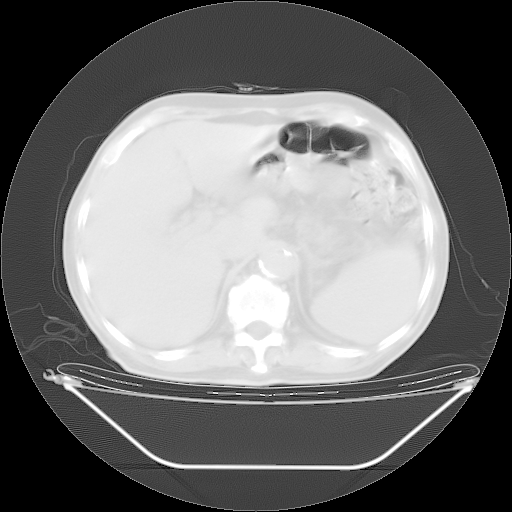

今天复查肺部CT,发现双肺广泛磨玻璃样改变。所以我把3月19日和5月9日相隔50天的肺部CT上传。请大家会诊。

2009年3月19日肺部CT片。

5月9日肺部CT(在4月27日齐鲁医院肺部CT描述部分肺组织磨玻璃样改变,12天后肺组织广泛磨玻璃样改变)